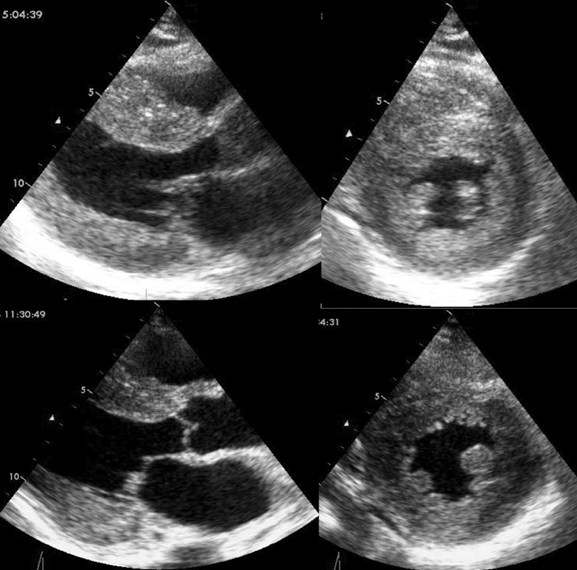

心アミロイドーシスの心エコー所見

上段はALアミロイドーシス、下段はATTRvアミロイドーシス

心エコー上は、両者の区別はできない。

ATTRwtの心エコー

ALアミロイドーシスと比べ、左室壁厚は厚く、左室駆出率は低下しているのが特徴である。